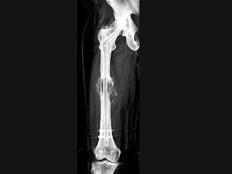

问题 男,18岁,右股骨肿瘤术后,出现大腿中段疼痛,夜间尤甚,结合CT图像,最可能的诊断是?(?)

选项 A.骨纤维肉瘤 B.尤文肉瘤 C.骨肉瘤 D.成骨性骨转移瘤 E.化脓性骨髓炎

答案 C